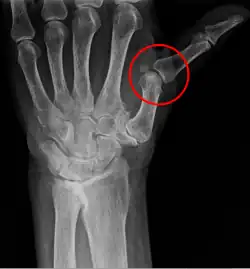

Una subluxación es un desplazamiento de una articulación por estiramiento de tejidos blandos. Este tipo de trastornos aprisionan nervios, desencadenando múltiples problemas físicos, reduciendo la movilidad articular, pues afectan directamente la biomecánica corporal. Cuando se aprisiona un nervio queda comprometida la funcionalidad articular asociada al mismo. Por tal razón las subluxaciones tienen un efecto dominó en perjuicio de la salud y el bienestar general del individuo.